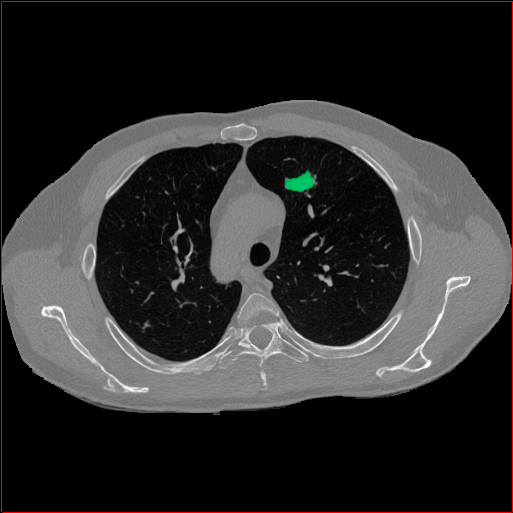

Lung Tumor

0.75×0.75×0.60.75\times 0.75\times 0.6

mm

512×512×512512\times 512\times 512

Refer to caption

Figure 5: MAISI-v2 segmentation-guided results for five types of tumors. We show results for different voxel spacing and volume size to demonstrate the flexibility of MAISI-v2. Different Hounsfield Unit window is used to better show the contrast between tumor and normal tissues.